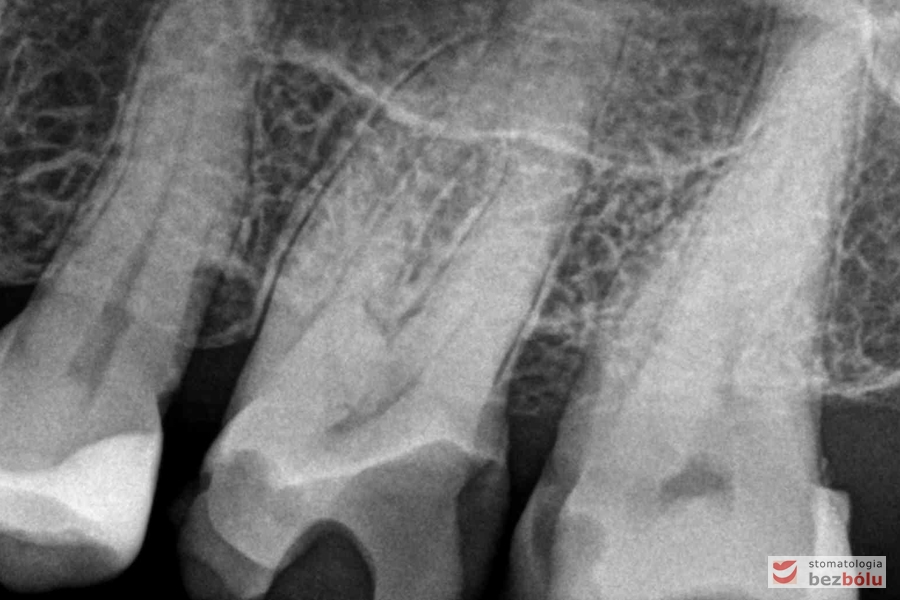

Radiowizjografia - jedynka górna prawa z niedopełnionym kanałem korzeniowym

Radiowizjografia – jedynka górna prawa z niedopełnionym kanałem korzeniowym